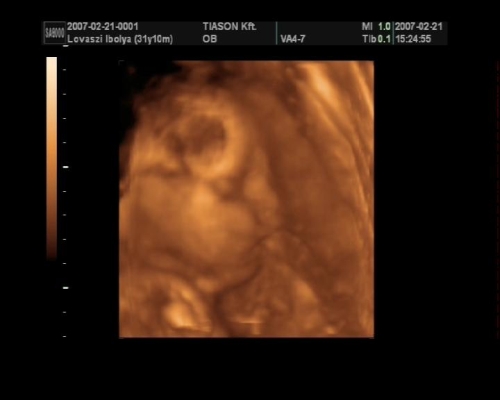

, de ami fura volt, a szívét a pocakom bal oldalán középtájban éreztem, felette pedig folyamatos rugdosást, vagy kalimpálást, De a másik oldalon ugyanott szintén... Lehet, hogy keresztben van???? De a múltkor már lent volt. Na kíváncsi vagyok kedden mit mutat az UH. Dehát azt csak lehetne látni rajtam, ha keresztben lenne...